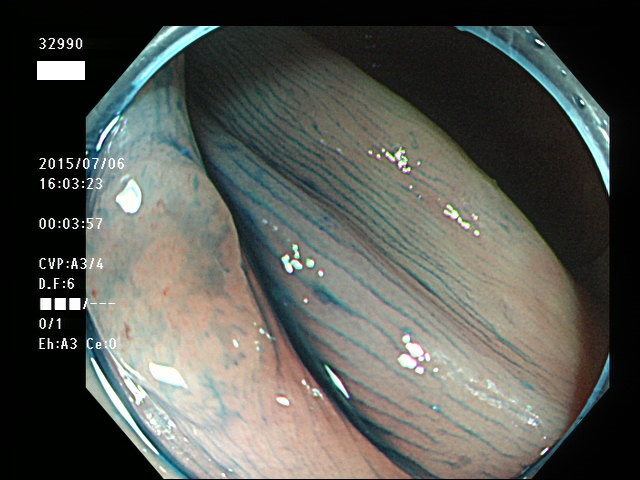

上記100名より抽出した平坦・陥凹型腺腫(=癌化の危険が高いが見落としやすい病変)の内視鏡写真

32901 32902 32903 32904 32905 32906 32907 32910 32911 32912 32915 32916 32918 32919 32920 32921 32922 32923 32924 32925 32926 32927 32928 32929 32931 32933 32935 32939 32941 32951 32953 32956 32957 32959 32961 32963 32964 32965 32967 32968 32971 32972 32973 32976 32978 32980 32981 32982 32986 32988 32989 32990 32994 32995 32998・・・・・・の55名